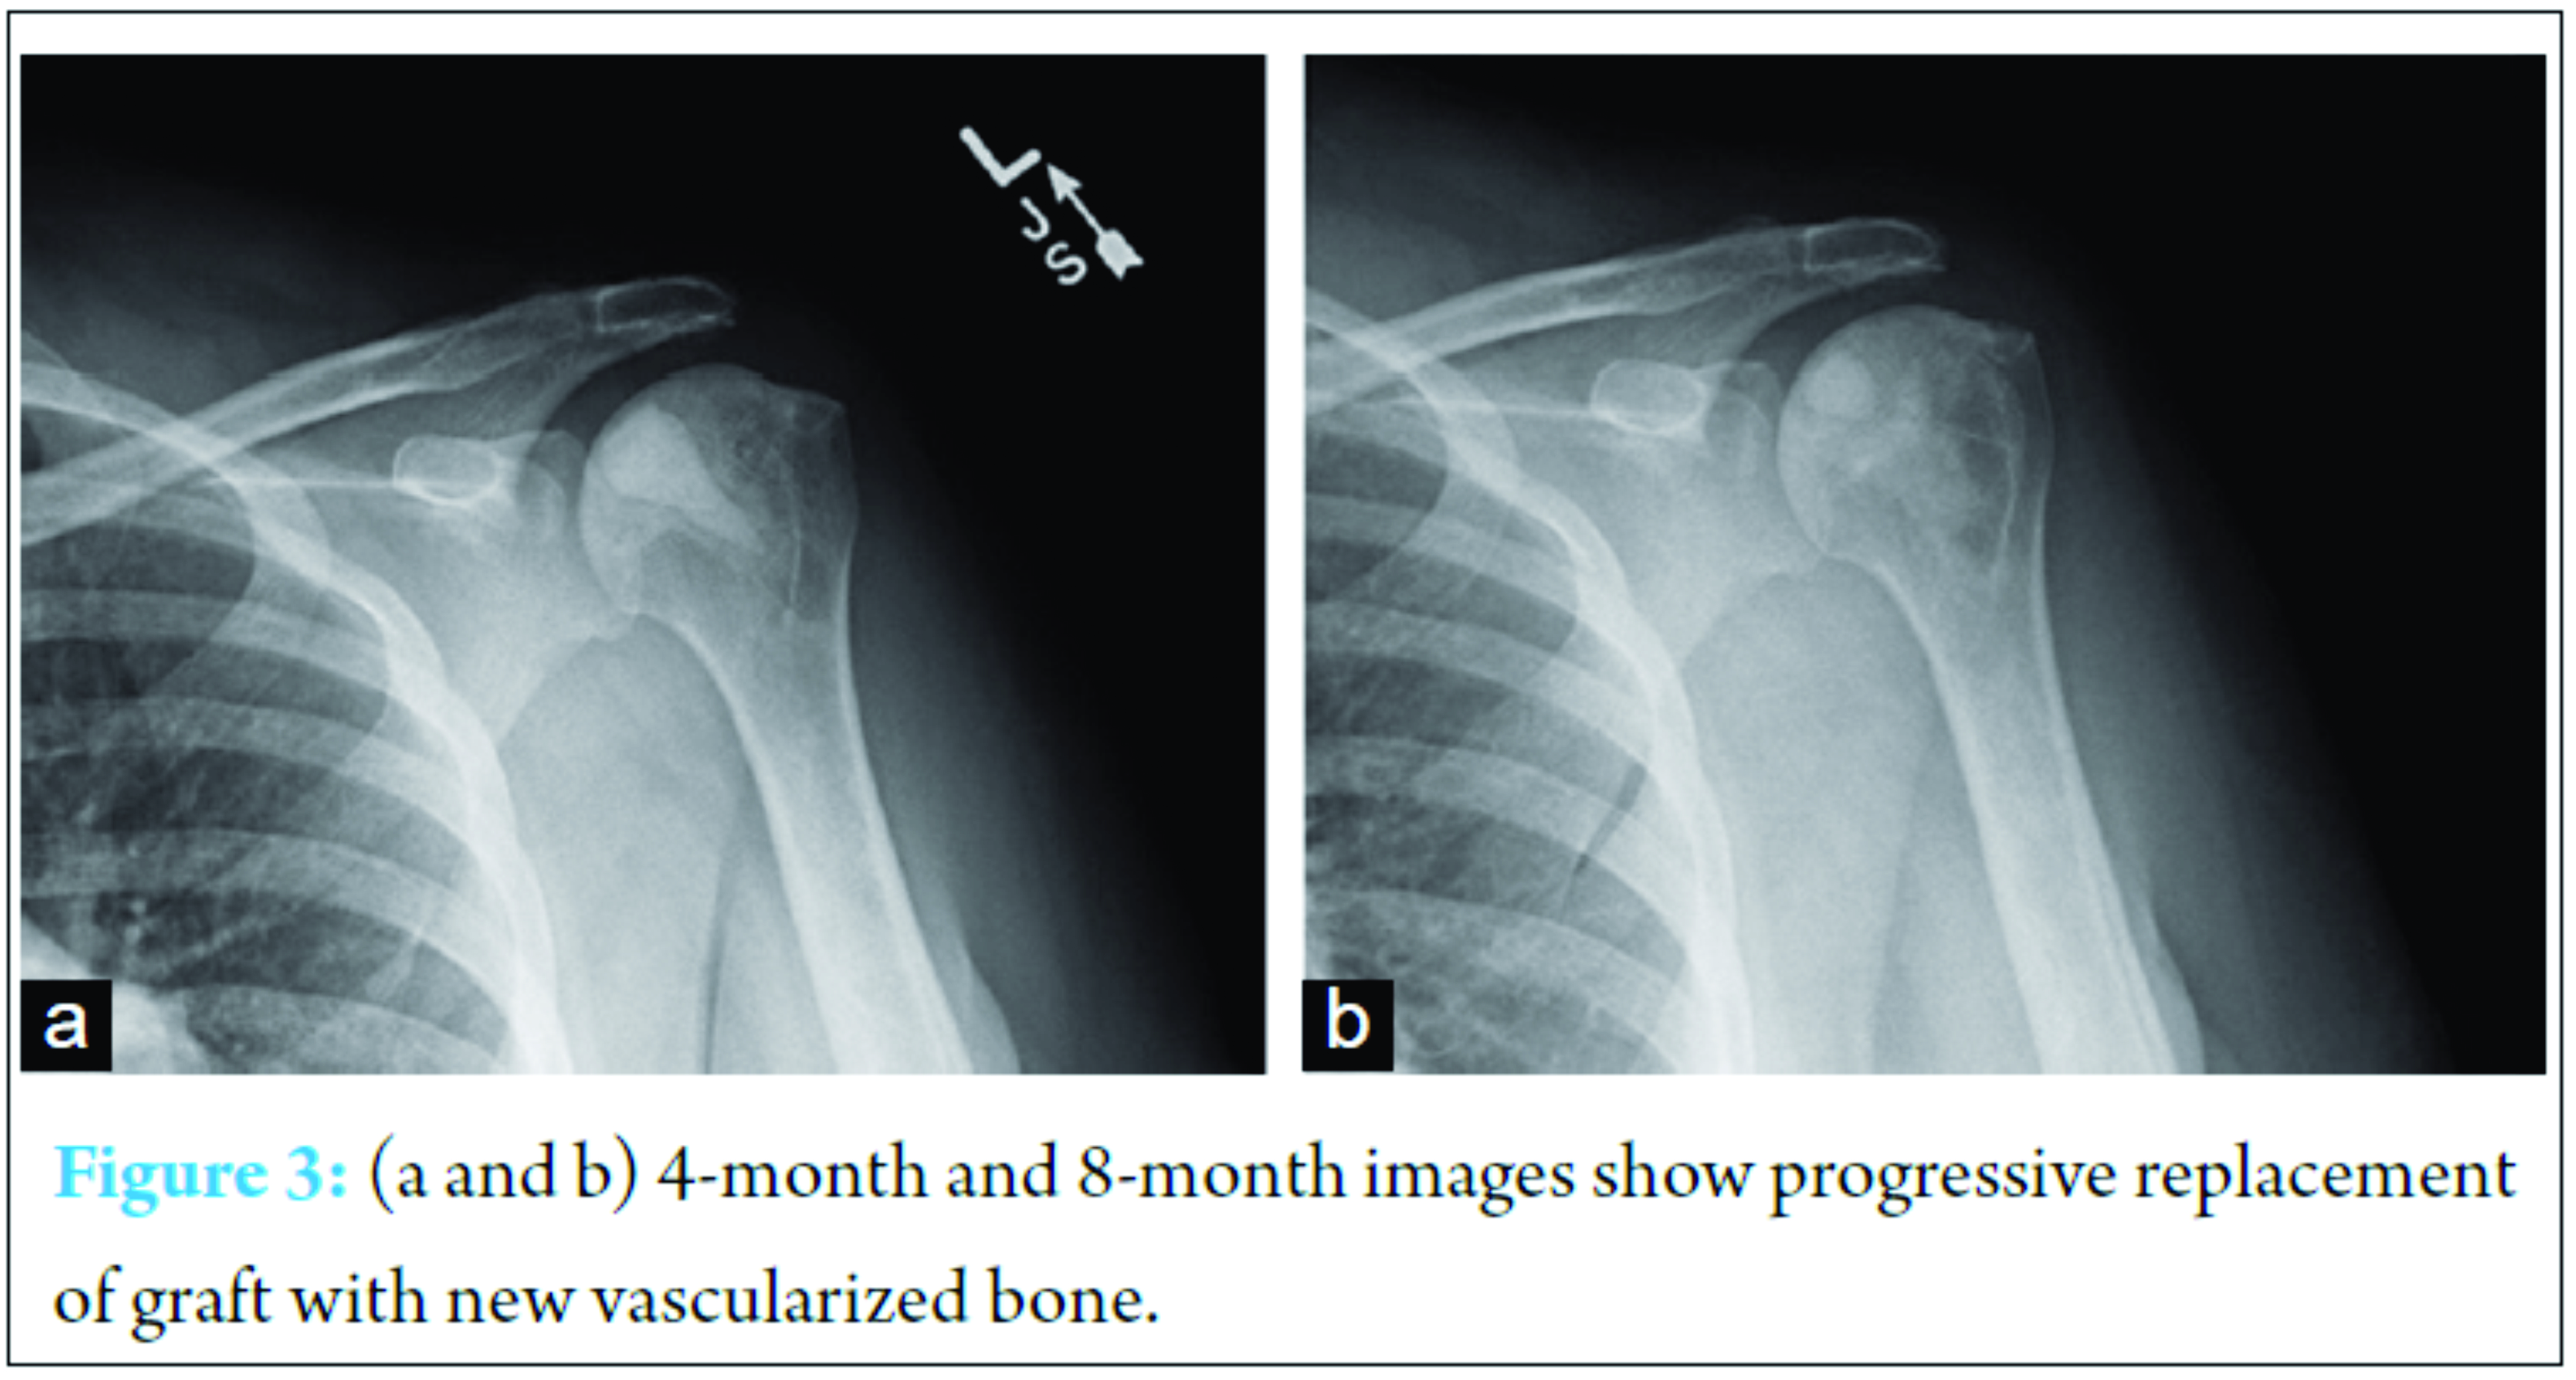

Staged surgery was then performed approximately 4-month apart using the identical technique on both shoulders. Our standard perioperative protocol for sickle cell patients was utilized. This consists of admission the evening before surgery to the internal medicine service with acquisition of routine blood work, intravenous hydration, and preoperative blood transfusion as indicated based on hemoglobin level [9]. Surgery was performed in the beach chair position with the c-arm coming in perpendicular to the patient. Diagnostic arthroscopy was performed to evaluate for intra-articular pathology and confirm that there was no significant chondromalacia, which would negate the benefits of the joint preservation procedure. In this case, arthroscopy revealed small partial thickness articular sided supraspinatus tears that were debrided but no visible chondral damage was present. Upon probing, the cartilage was quite soft over the areas of AVN noted on MRI. Under fluoroscopic guidance, a guide wire was directed into the center of the region of AVN, which was done via a small deltoid splitting approach laterally. The arthroscopic probe was placed in the center of the most depressible cartilage region on the head and utilized fluoroscopically to guide pin placement. Once the guide wire was in the center of the defect, an expandable reamer was utilized and the necrotic bone was removed (Fig. 2).  The arthroscope is critical in this stage to allow complete extraction of necrotic subchondral bone while ensuring no penetration of the cartilage. After full decompression was performed, synthetic bone graft (PRO-DENSE, Wright Medical) was injected under fluoroscopy and direct visualization. Given the immediate structural integrity of the graft, maximal removal of necrotic segments was attempted. Care was taken under fluoroscopic guidance not to penetrate the articular surface and no cartilaginous defects were encountered. For both procedures, the standard sickle cell protocol was followed with overnight admission for intravenous hydration followed by discharge with 2 weeks of deep venous thrombosis (DVT) chemoprophylaxis. She was allowed activity as tolerated and physical therapy initiated 2 weeks after each surgery. At 8-month follow-up from the index procedure, she is asymptomatic with a full range of motion on the first shoulder and some mild residual stiffness in the second shoulder (4-month follow-up). Radiographs demonstrate incorporation of the bone graft without evidence of joint collapse or further AVN (Fig. 3).

The arthroscope is critical in this stage to allow complete extraction of necrotic subchondral bone while ensuring no penetration of the cartilage. After full decompression was performed, synthetic bone graft (PRO-DENSE, Wright Medical) was injected under fluoroscopy and direct visualization. Given the immediate structural integrity of the graft, maximal removal of necrotic segments was attempted. Care was taken under fluoroscopic guidance not to penetrate the articular surface and no cartilaginous defects were encountered. For both procedures, the standard sickle cell protocol was followed with overnight admission for intravenous hydration followed by discharge with 2 weeks of deep venous thrombosis (DVT) chemoprophylaxis. She was allowed activity as tolerated and physical therapy initiated 2 weeks after each surgery. At 8-month follow-up from the index procedure, she is asymptomatic with a full range of motion on the first shoulder and some mild residual stiffness in the second shoulder (4-month follow-up). Radiographs demonstrate incorporation of the bone graft without evidence of joint collapse or further AVN (Fig. 3).